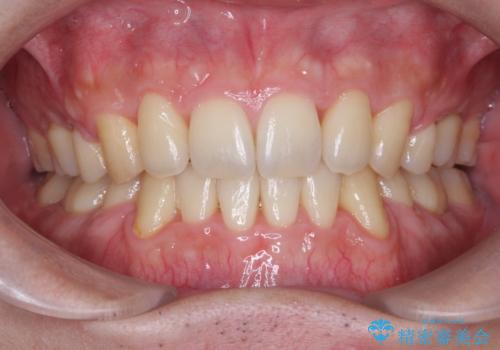

前歯のデコボコを改善 インビザライン矯正

担当医 藤巻太一朗